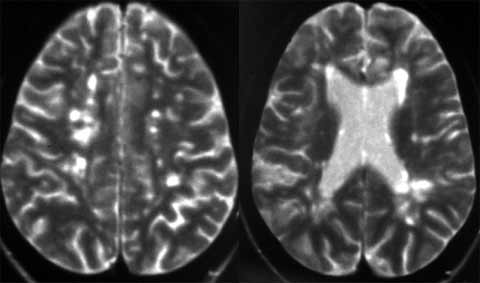

Оценка динамики активности ремиттирующего и прогрессирующего рассеянного склероза.

Рис. 3. Обширный атрофический процесс с крупными очагами демиелинизации при первично-прогрессирующем РС. (Слева) - полушария, (Справа) - ствол головного мозга.